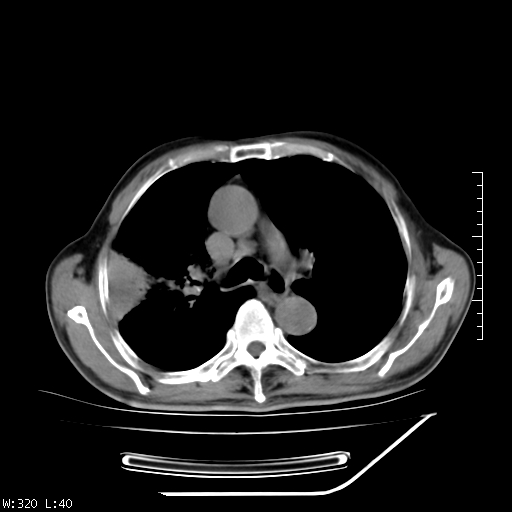

标题: CT23994:男、72、咳嗽、气短两月余,近来消瘦。 [打印本页]

标题: CT23994:男、72、咳嗽、气短两月余,近来消瘦。

右上肺实变,与胸膜关系密切,右肺容积缩小,隆突下淋巴结增大,考虑1 肺结核 2 肺癌

右上肺大片状密度增高影,与胸膜关系密切,内见低密度透亮影,胸膜下可见三角形不张影,左下肺沿支气管走形结节影,纵膈内淋巴结显示。考虑结核并疤痕性不张可能性大,建议穿刺活检,排除肺泡癌。